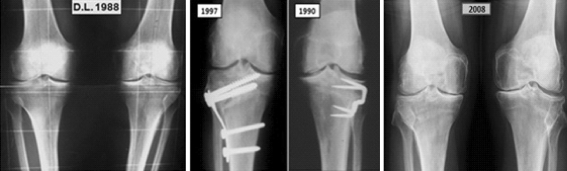

The healing delay was 70 days for the opening and 55 days for the closing wedge osteotomy. The mean valgus angle remaining at follow-up of 15 years was 2° after opening and 4° after closing osteotomies (Fig. 2). The position of the patella was studied using the Caton index [4]. The calculations showed 6% patella alta after opening wedge and 7.5% baja were found in the closing series. These fairly high figures support the rigorous operative techniques described [25].

Fig. 2.

A 62-year-old male patient (D.L.) had a medial meniscectomy in the left knee in 1988. Two years later, we proceeded to a high tibial closing osteotomy for osteoarthritic varus. Fixation was done by staples. At that time, one could also note an osteochondritis on the left medial femoral condyle. This intervention allowed him a painless knee and normal activity until 1997 when he benefited from another closing wedge osteotomy on the right knee. For several years after the osteotomies, the patient could walk and run without any pain. At the last follow-up in 2008, he was still satisfied and active, walking without crutches. Meanwhile, his left medial condyle osteochondritis healed even though the arthritic radiological aspect was slightly worsening